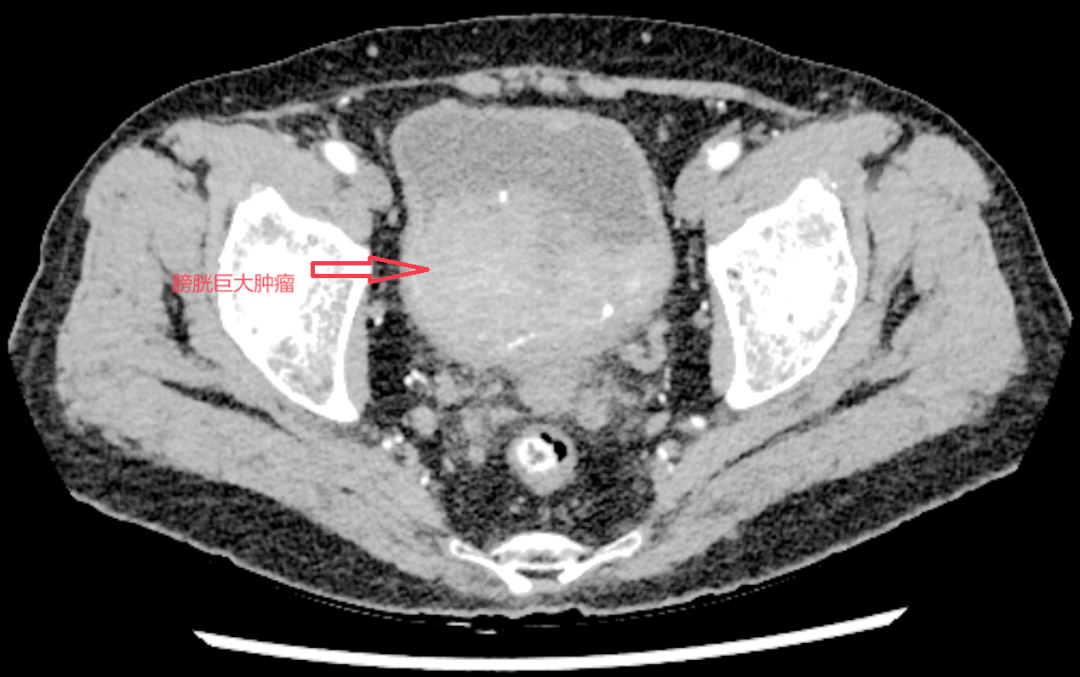

▲术前增强CT片

据悉,该患者因出现无痛性肉眼血尿前往我院就诊,后被确诊为肌层浸润性膀胱癌。膀胱癌根治术是治疗该疾病的有效方法,但对于一位94岁高龄、身体各器官功能均已衰退、并可能伴有多种基础疾病的老人来说,手术耐受性差,麻醉风险极高,术后恢复困难,历来被视为外科手术的“高龄禁区”。